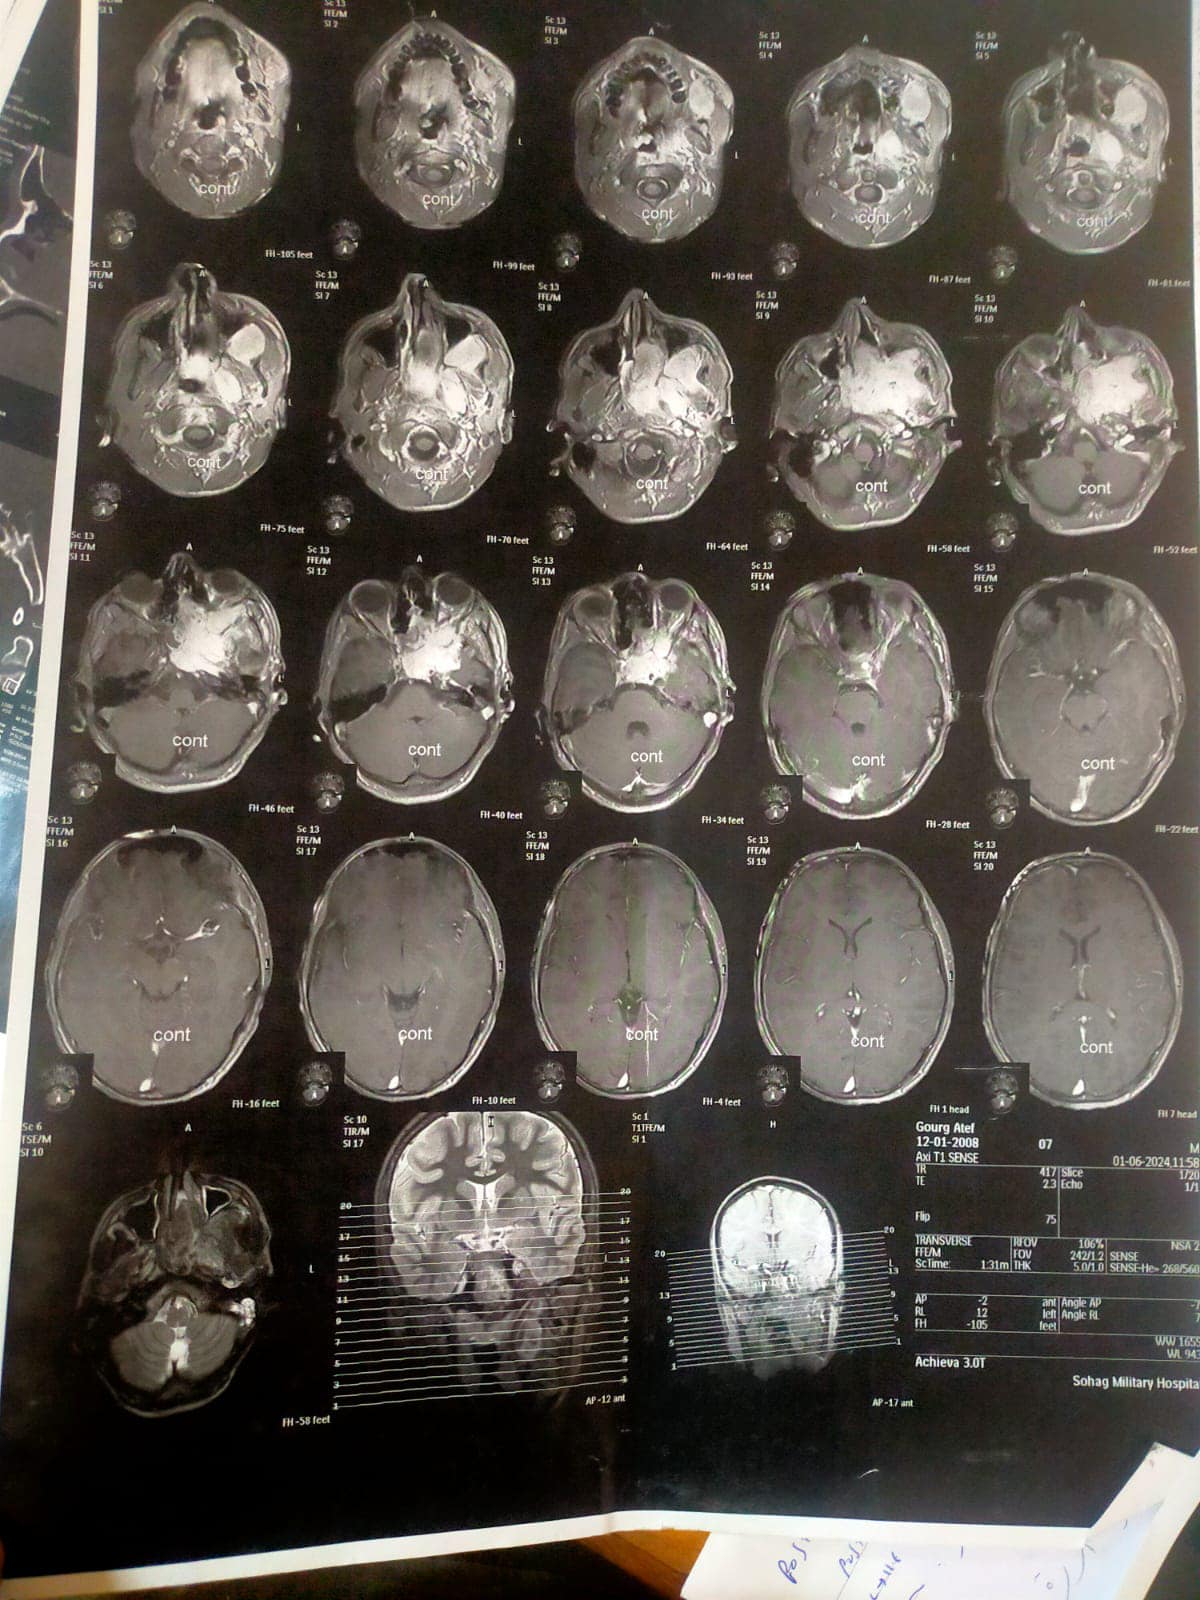

الجامعي من استئصال ورم دموي (انجيوفيبروما) بالأنف ممتد إلى الجيب الأنفي الوتدي و ملتصق بالشريان السباتي وممتد إلى المخ، لشاب في مقتبل العمر ١٦ سنة يدعي “ج. ع. ف” بمركز المنشاه، وذلك في عملية استغرقت ٥ ساعات متواصلة.

وقال الدكتور سمير عبدالمجيد مدير مستشفي الطوارئ بالحرم الجامعي الجديد، أن المريض وصل الي المستشفي بحالة انسداد الأنف وتاريخ مرضي لنوبات نزيف شديدة ومتكررة من الأنف كادت تودي بحياته، فعلي الفور تم إنهاء إجراءات دخول المريض بالقسم، وعمل الفحوصات المخبرية وشملت إجراء تحاليل دم وفصيلة دم وتجهيز ٣ أكياس دم ، وأشعة مقطعية ورنين بالصبغة، وأشعه مقطعية على الأنف والجيوب الأنفية بالصبغة، ورنين على المخ وقاع الجمجمة بالصبغة، وعقب الإنتهاء من التجهيزات اللازمة تم دخوله غرفة العمليات وخرج في حالة مستقرة.

ومن جانبه أضاف الدكتور محمد عبدالقادر سلطان رئيس قسم الأنف والأذن والحنجرة، أنه علي الفور تم تشكيل فريق طبي علي درحة عالية من المهارة نظراً لخطورة العملية ودقتها، فتم حقن الشرايين المغذية للورم الدموي قبل العملية لتقليل النزيف اثناء العملية بالأشعة التدخلية، وعقب العملية خرج المريض في حالة صحية مستقرة.